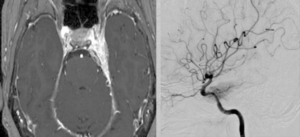

視力障害、記銘力障害で発症した頭蓋咽頭腫を両側前頭開頭、anterior interhemispheric approachで切除しました。トルコ鞍部や鞍上部にはほとんど局在しないためtranslamina-terminalis approachを選択しました。視床下部動脈を温存し、内減圧を繰り返し、焼き鳥テクニックとリングキュレットで狭い術野から腫瘍を起こして摘出しました。術後年齢が比較的若かったためかすぐに覚醒しました。